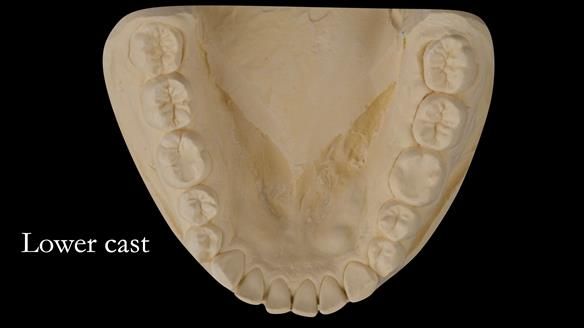

The clinical situation and treatment process is shown in detail below with photographs. I (Finlay Sutton) provided the clinical work and Rowan Garstang provided the technical work.